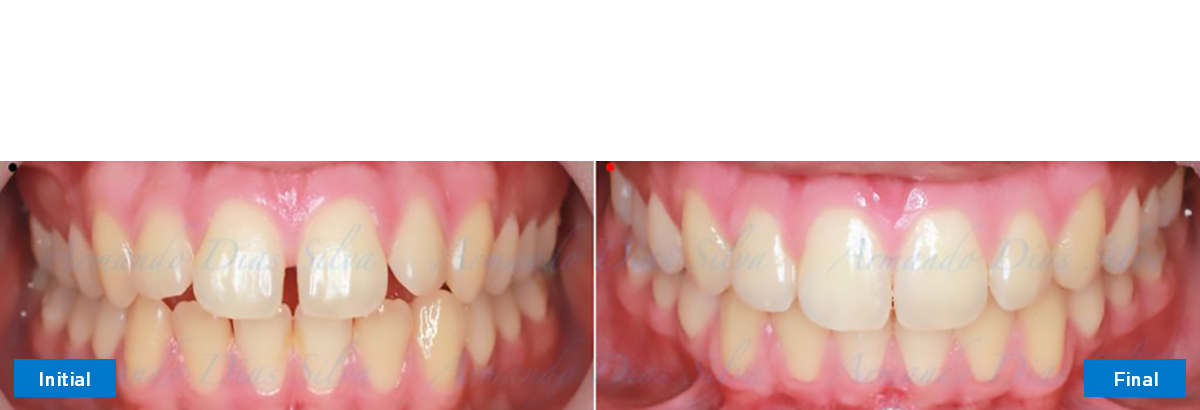

Se logran todos los objetivos principales:

• Molares de clase I logrados con distalización y sin elásticos

• Sin cambios en la posición del cóndilo

• Sin expansión maxilar, respetando la envoltura periodontal

• Incisivos inferiores retroinclinados, que mejoran la estabilidad a largo plazo

Retención: Arco superior retenido con retenedor transparente. Arco inferior retenido con retenedor lingual unido de canino a canino.